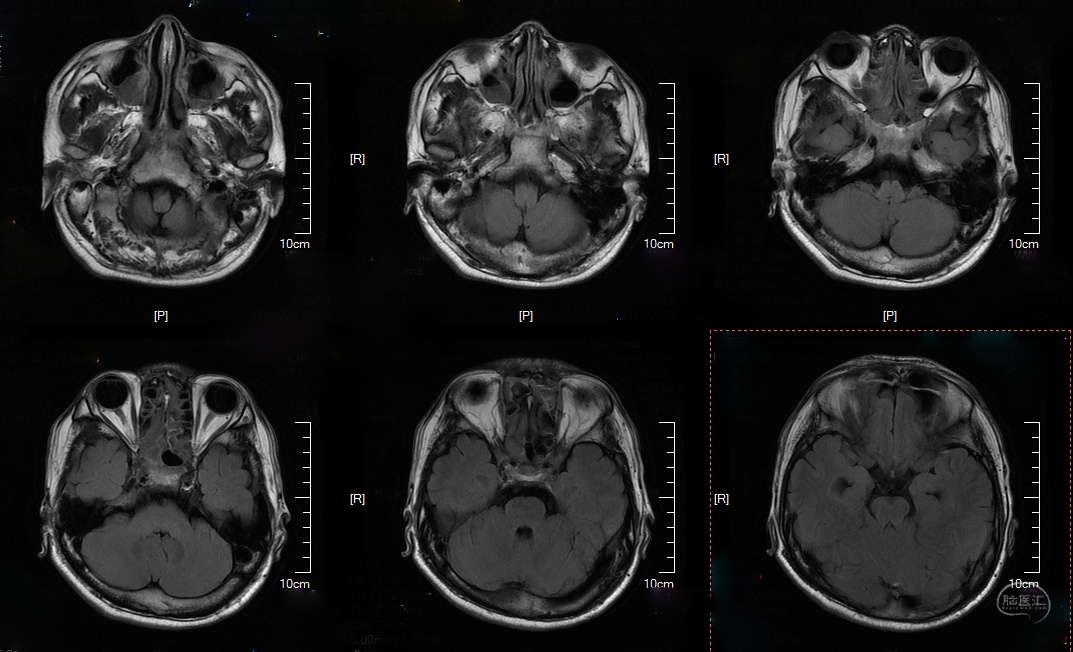

头颅CT及MRI:

T2: